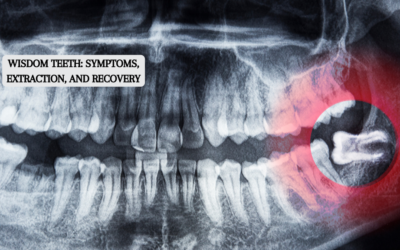

Wisdom Teeth: Symptoms, Extraction, and Recovery

The wisdom teeth, often called third molars, are the last set of teeth that erupt from your mouth's back corners. While in good condition and alignment, they can be a great help, but they frequently produce issues that necessitate their removal. This article will...